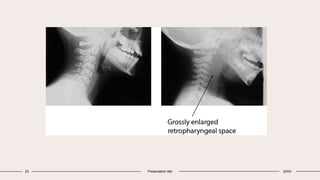

RETROPHARYNGEAL ABSCESS

Neck radiographs:

• Abscess cavity may be evident on lateral neck

radiographs, andanterior displacement of the

esophagus and upper pharynx may be present.